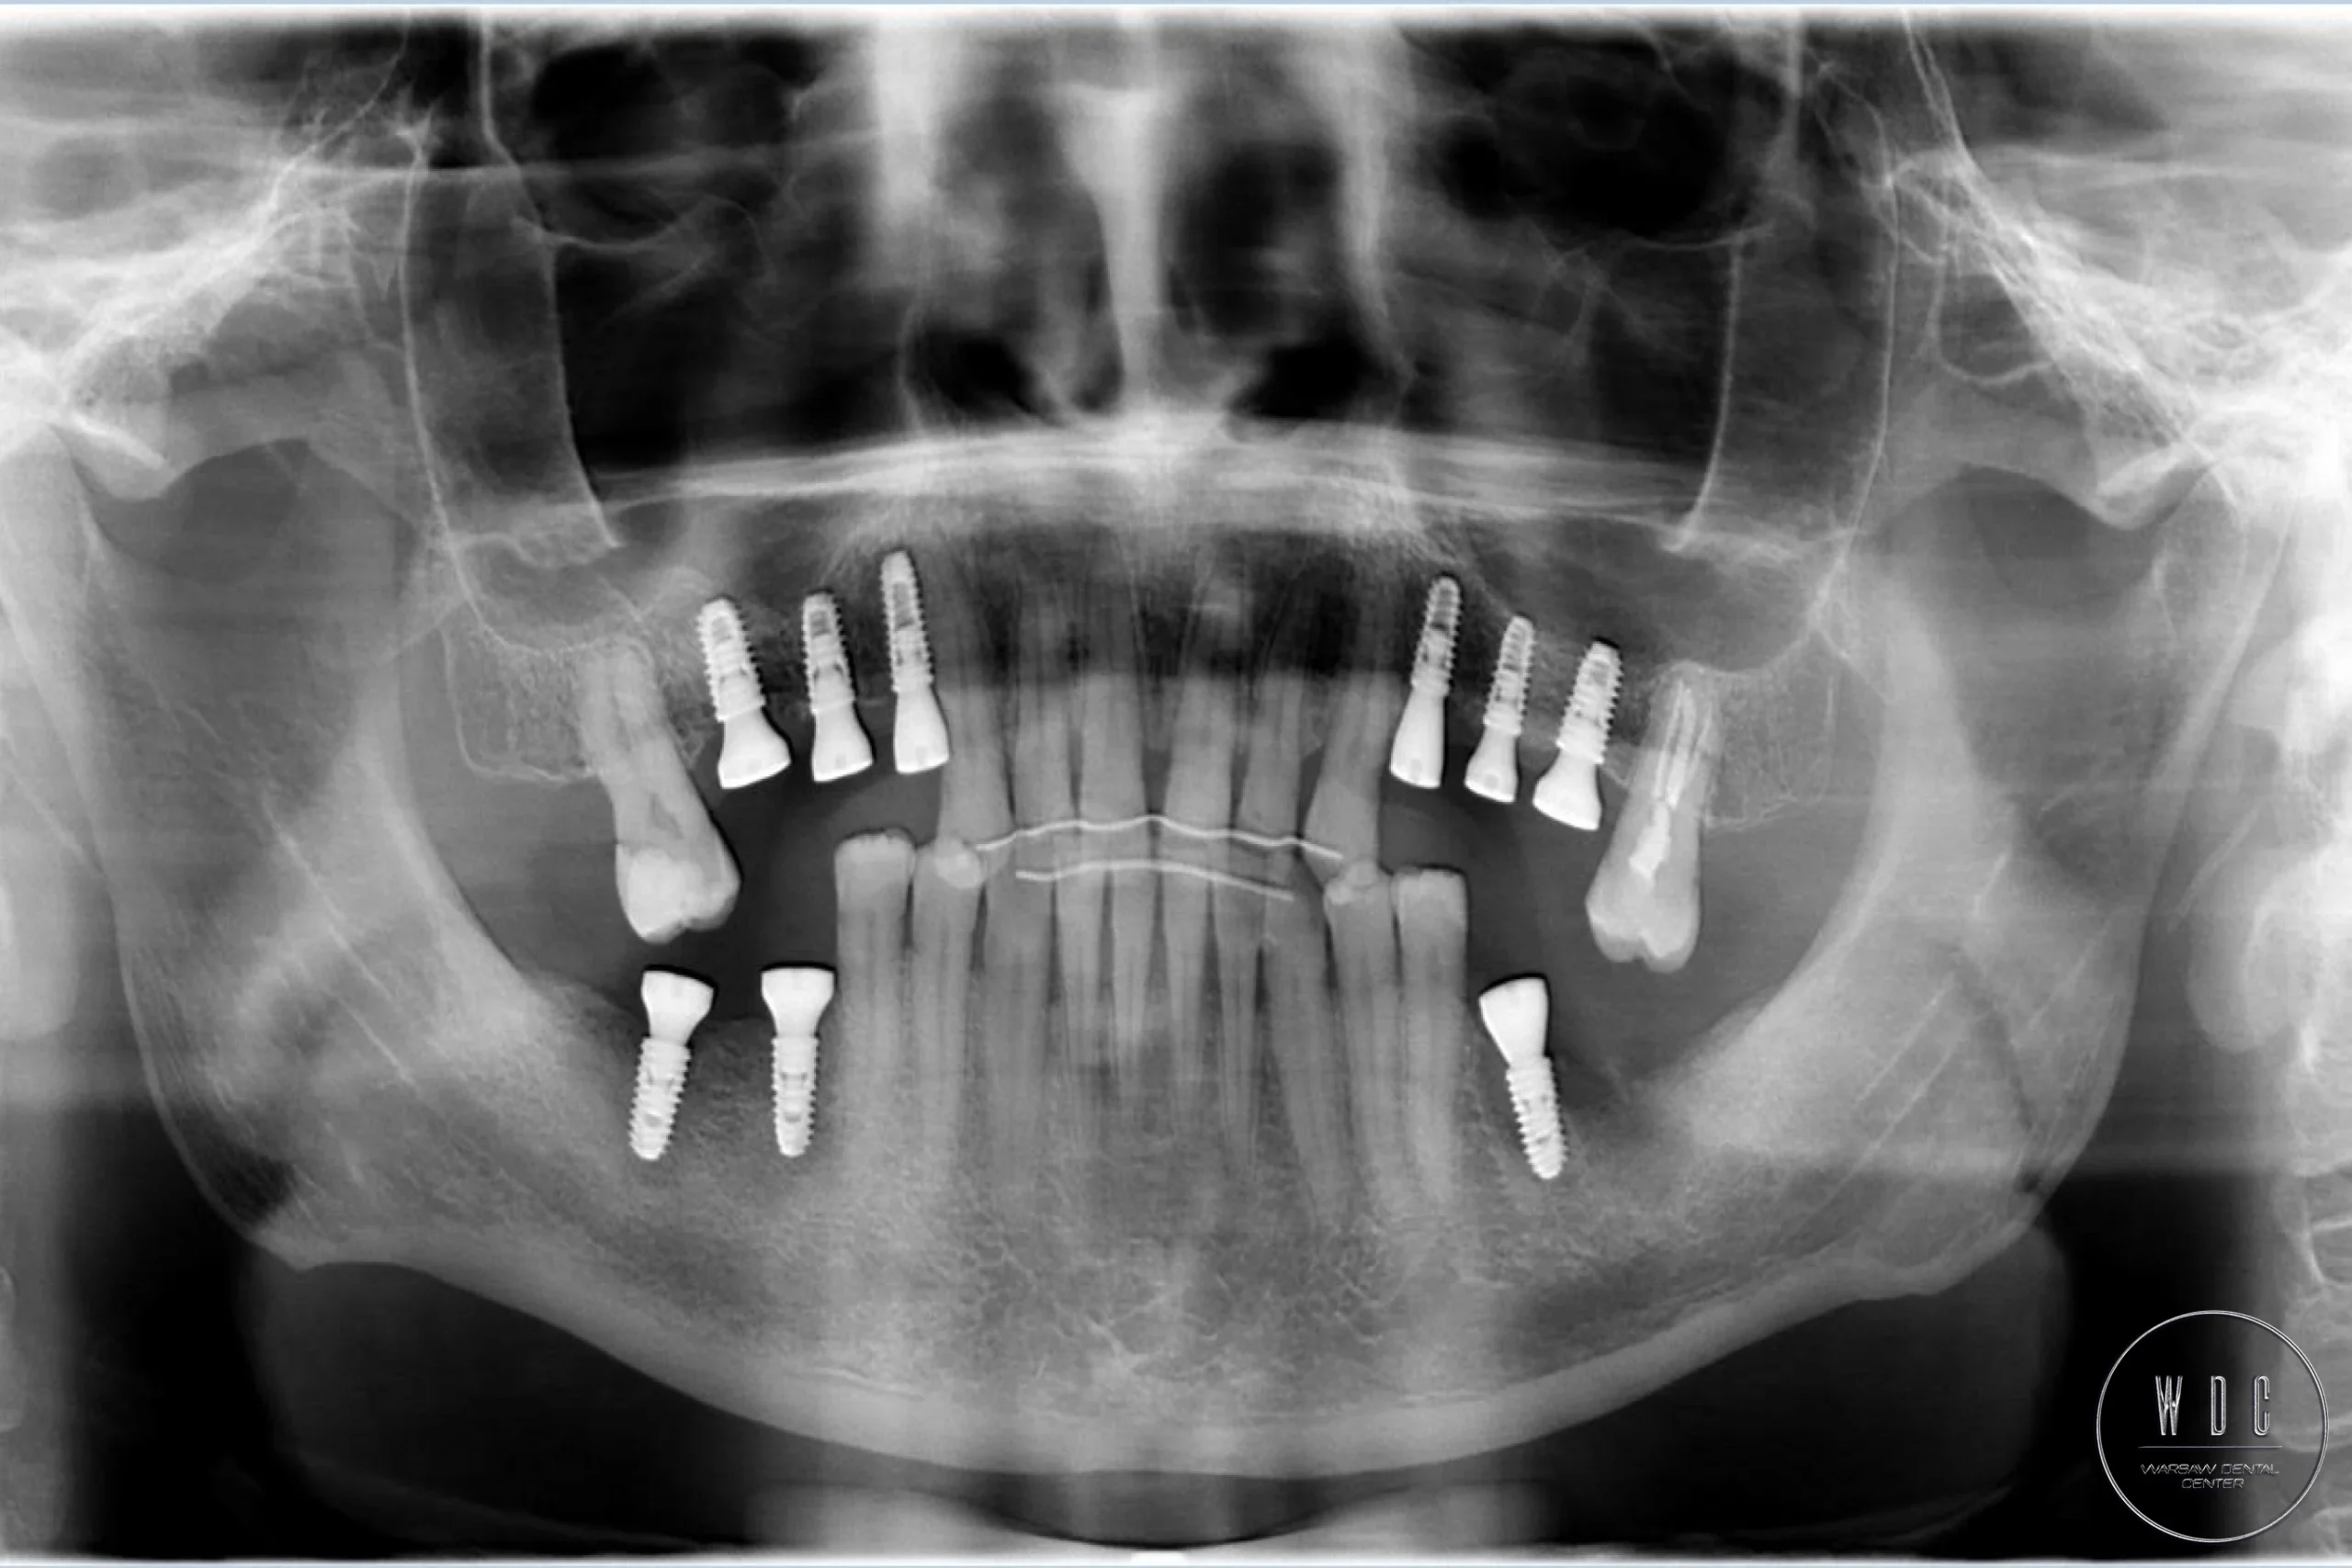

Talk to us about tooth reconstruction with implants. Our modern implantation technology, based on the use of surgical templates, provides a more comfortable experience, better results, and a higher success rate for the procedure.

This technique is an advanced approach that requires meticulous planning and the use of advanced 3D imaging to precisely place dental implants. This ensures perfect placement, significantly reduces discomfort, and speeds up recovery time. The next step after implantation is the placement of a healing screw and, after a specified time determined by the surgeon, the placement of a crown on the implant.

Step 2: Diagnostics

Examinations such as X-rays or CBCT scans to assess the jawbone and plan the implant placement.

Step 4: Implant Placement

Surgical placement of the implant into the jawbone under local anesthesia.